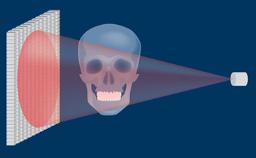

通过辅助诊断检查,可确定和评估位点特定的外科和修复要求。这有助于尽量减少种植治疗后的并发症和失败风险。

- 在制定种植治疗计划时识别辅助诊断检查的适应症

- 描述不同的辅助诊断检查